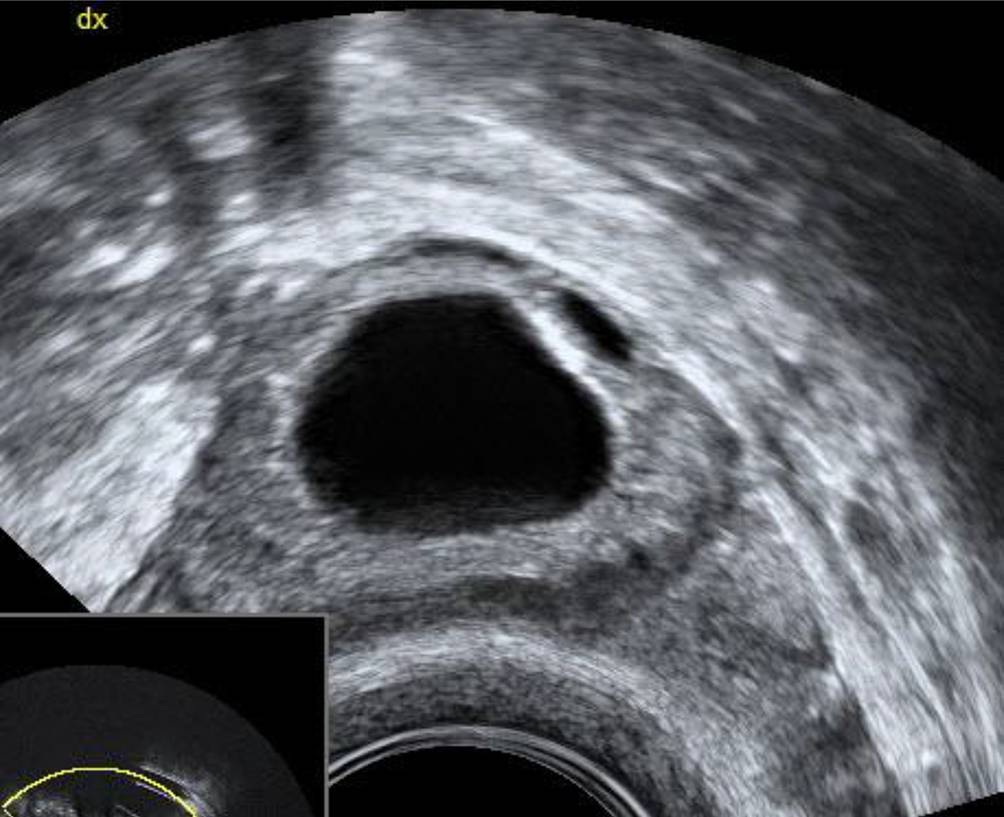

Abb. 3

Dieses Corpus luteum hat eine große „central fluid-filled cavity“ ohne Zeichen von Koageln im Inneren. Dieser Befund wird auch „follicular refilling“ genannt

Es werden wenige oder gar keine Koagel gesehen, dafür eine „central fluid-filled cavity“ (CFFC), ein flüssigkeitsgefüllter Raum im Zentrum des Corpus luteum, der über einige Tage bestehen kann. Dieser Befund wird von manchen Autoren auch als „follicular refilling“ bezeichnet, da in solchen Fällen das Corpus Luteum wie ein präovulatorischer Follikel aussehen kann (Abb. 3 und 4). Bei einer Nachfolgeuntersuchung einige Tage später sind diese Strukturen meist kleiner.

Sehr hilfreich ist der Farbdoppler bei der Feststellung eines Corpus luteum – die für die endokrine Aktivität des Organs nötige periphere Vaskularisation zeigt sich in einer meist kreisrunden, 1–2 cm großen charakteristischen Struktur im Ovar – im Ultraschalljargon, seit es den Farbdoppler gibt, als „ring of fire“ bekannt. Diese Vaskularisation nimmt rund 10 Tage nach der Ovulation ab, mit Beginn der Monatsblutung ist sie kaum mehr vorhanden. Solide Strukturen im Inneren der Flüssigkeit kann man nur dann sicher als Koagel beschreiben, wenn sie im Farbdoppler nicht vaskularisiert sind. Wären die echodensen Strukturen innerhalb der Flüssigkeit in Abb. 4 vaskularisiert, müsste die Verdachtsdiagnose auf ein Muzinkystom oder ein Malignom lauten und der Befund müsste nach den IOTA-Kriterien beurteilt werden [1].